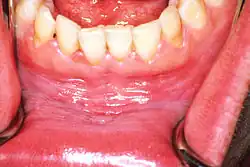

![]() | |

| Leukoplakia on the inside of the cheek | |